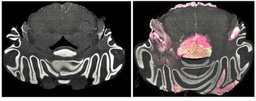

Protocols to genetically modify T cells to express CARs (for example by using retroviral vectors) typically work by inserting CAR-encoding DNA randomly over the cell’s genome. This arbitrary pasting of DNA can lead to disruption of endogenous genes (a potentially oncogenic process in itself) and limits the control over CAR expression levels. However, new technologies that enable targeted genetic manipulation (such as clustered regularly interspaced short palindromic repeats (CRISPR)–Cas9 genome editing) have been developed in the past few years. In a new study published in Nature, Michel Sadelain and colleagues from the Memorial Sloan Kettering Cancer Center, New York, employed CRISPR–Cas9 genome editing to insert a CD19-specific CAR into the TRAC locus of T cells (Figure 1). The authors show that CAR T cells produced with this method remain active for longer and are more efficacious than CAR T cells generated by random integration of CAR-encoding DNA in prolonging survival in a mouse model of acute lymphoblastic leukaemia. The results suggest that a tighter control over CAR insertion and expression could potentiate existing methods to generate tumour-specific T cells.

Figure 1 | Targeted insertion of a CAR in T cells. a, CARs can be inserted at a random location into the genome of T cells. If the CAR is expressed constitutively, the cells often become dysfunctional and enter a state called exhaustion. b, CRISPR–Cas9 and a guide RNA directed to the 5’ end of the first exon of TRAC was used to replace the cell’s T-cell receptor (TCR) gene with a CAR-encoding sequence. c, The modified T cells now express only the CAR, whose expression is directed by the endogenous regulatory elements of the TCR. These T cells operate in a quasi-physiological way, and do not undergo early exhaustion. Reproduced from Maus, M. V. Nature doi:10.1038/nature21506; SpringerNature.

By replacing the endogenous T-cell receptor (TCR, whose α constant chain is encoded in TRAC), the CAR is expressed under the control of the endogenous regulatory genetic elements that modulate expression of the original receptor. Sadelain and colleagues demonstrate that targeted CAR integration translated into several advantages that support improved in vivo therapeutic performance: the method avoids random integration of DNA in the cell’s genome (which can have detrimental consequences); also, as the endogenous TCR is no longer expressed, the possibility that these CAR T cells promote autoimmune responses, in cases where the original TCR recognized self-peptides, is limited; finally, as the CAR is controlled by the same genetic elements that regulate the expression of the endogenous TCR, CAR expression is regulated physiologically.

The physiological regulation of CAR expression is an important achievement. Strong and prolonged TCR activation signals, which can occur as a consequence of TCR overexpression, are known to induce a state of ‘exhaustion’ in T cells that leads to loss of function. The same phenomenon has been described in T cells modified by random, multiple integration of antigen receptors. By contrast, targeted insertion of the CD19-specific CAR to the TRAC locus avoids this premature dysfunctional behavior of the CAR T cells, and ultimately translated to superior therapeutic performance in eliciting an immune response to tumours.